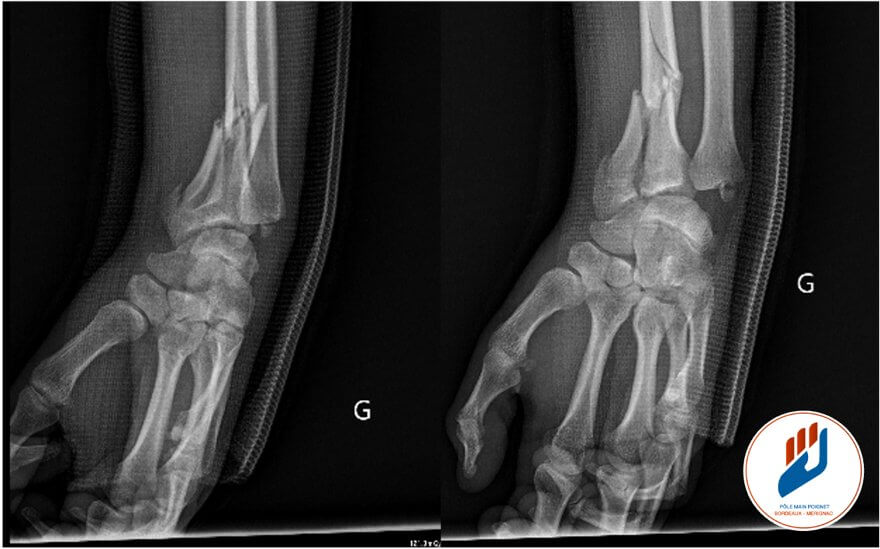

Fracture du radius distal

Lors d’un traumatisme, l’extrémité du radius peut se fracturer. La fracture peut être extra-articulaire (sans toucher le cartilage) ou être intra-articulaire lorsqu’elle atteint l’une ou l’autre de ces articulations. L’atteinte articulaire est une notion importante, car le cartilage ne cicatrise pas comme l’os. Une fracture qui pénètre dans l’articulation radio-carpienne ou la RUD expose à un risque plus élevé de raideur, de douleurs persistantes et à plus long terme, d’arthrose si les surfaces articulaires ne sont pas parfaitement réalignées.

Il existe plusieurs types de fractures du radius distal :

- fractures extra-articulaires / fractures intra-articulaires touchant une ou plusieurs surfaces articulaires

- fractures simples ou comminutives (en plusieurs fragments),

- fractures déplacées ou non déplacées,

- fractures associées à une atteinte de l’ulna ou du styloïde ulnaire, parfois révélatrices d’une atteinte de la RUD ou du ligament triangulaire (TFCC).